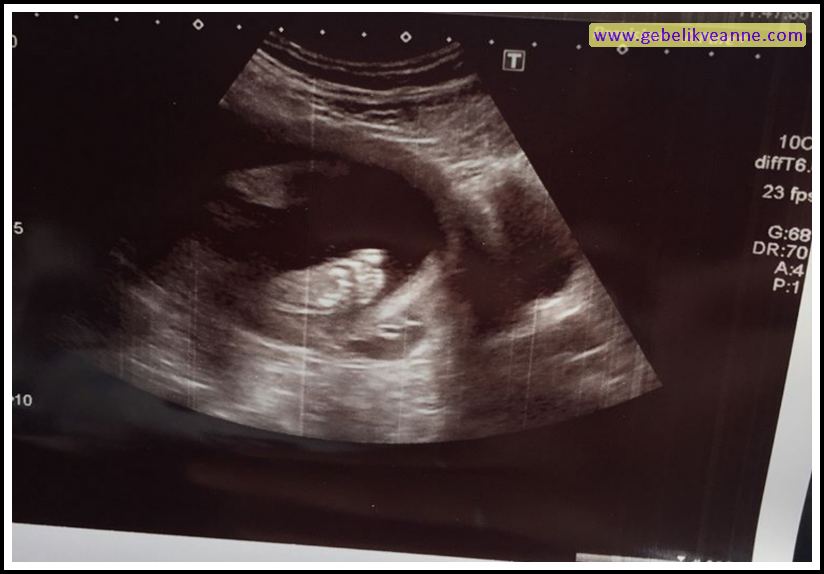

24 Haftalık Gebelik Ultrason Görüntüleri, Hareketleri

24 haftalık bebek görüntüsü nasıl olur? 24 haftalık bebek kaç gram olur?: 24 haftalık bebek gelişimi kas ve kemik dokusunun da hızla gelişmesi anlamına gelir.